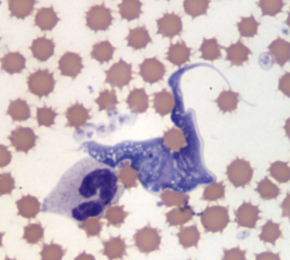

how do you ID Trypanosoma cruzi

EXTRAcellular - banana-shaped with a thin, whip-like tail (flagellum) used for “swimming”